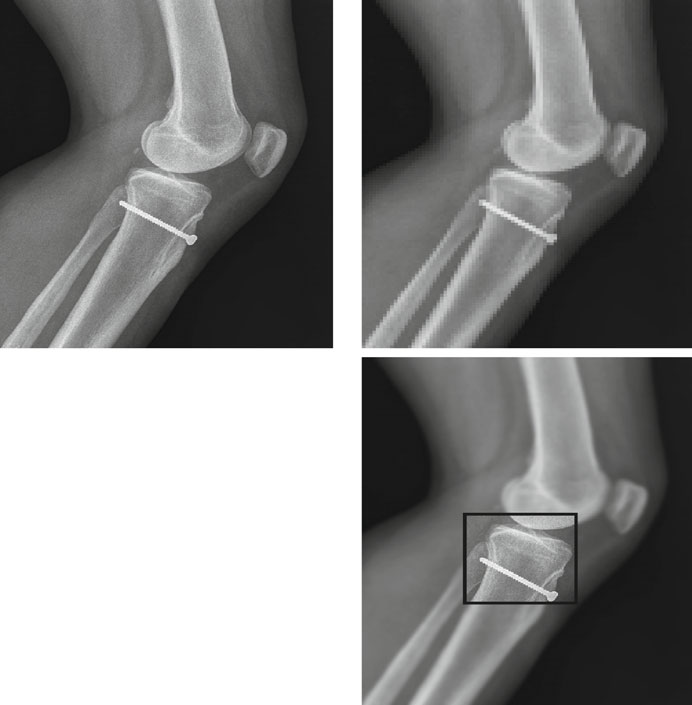

Identificadores Únicos (UIDs): Por Que São Globais?

Imagine uma imagem de raio-X copiada, anotada e enviada para telerradiologia em outro país. Agora existem várias instâncias da mesma imagem original, cada uma potencialmente modificada. Como diferenciá-las? Através de UIDs distintos para cada instância. A estrutura de um UID é <org root>.<suffix>, onde o root identifica a organização e o sufixo garante unicidade dentro do escopo.